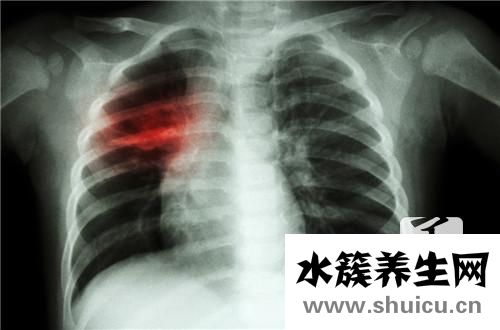

兒童很小,免疫力差,很容易患支氣管炎。 除了開出可靠的藥物外,他們通常應多吃一些有助于緩解咳嗽,滋養肺臟和化痰的食物,并適量喝些百合粥。 您還可以喝一些甜杏仁粥,對健脾,胃和肺有很好的作用。 另外,山藥粥和梨粥可以充分發揮輔助治療的作用。

小二支氣管炎的飲食療法方式